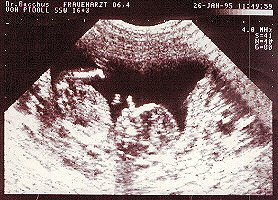

Bilder Chantal: Image 1 of 30